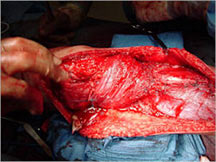

Surgery:

- Wide surgical resection/limb salvage

- Amputation for large unresectable tumors and other rare instances

Limb Sparing Surgery

- Surgical principles are the same as those employed for conventional osteosarcoma

- Nowadays, most patients can be treated with a limb sparing resection instead of an amputation

- Prosthetic replacements, cadaver allografts, vascularized bone grafts as well as other methods have been used to reconstruct extremities after tumors are removed